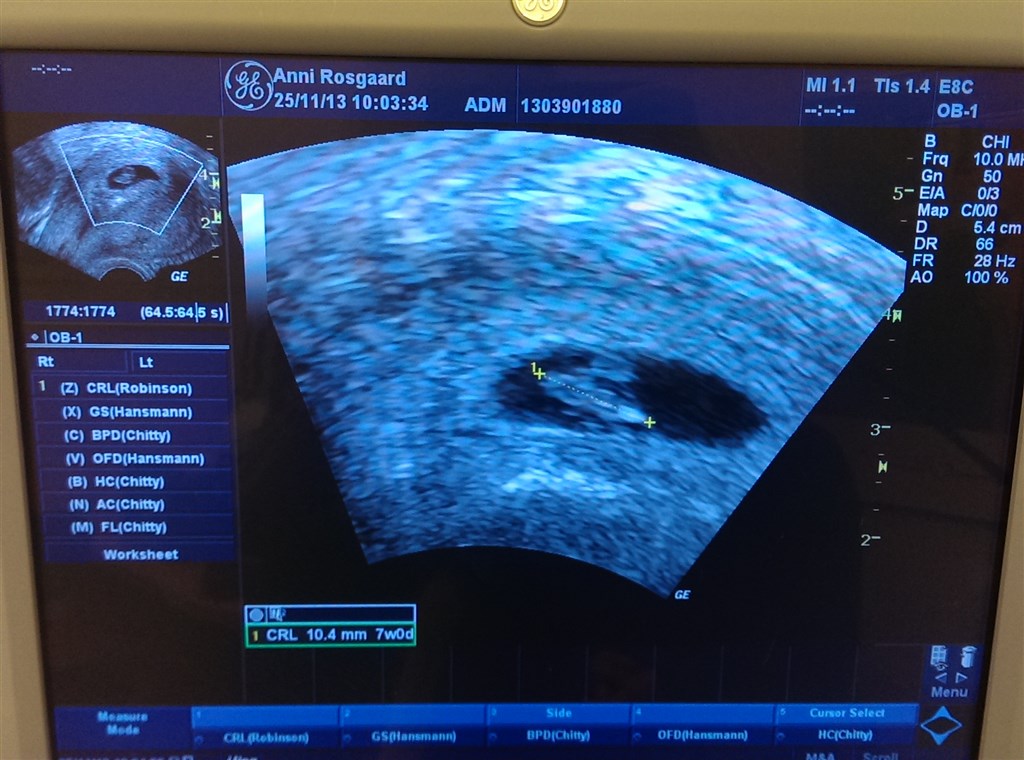

Jeg var til "7 ugers"/tryghedsscaning i tirsdags,

Mest fordi mit forløb på fertilitetsklinikken skulle afsluttes, men fik af vide alt var godt og spunk lå og puttede med sin madpakke

Fik afvide jeg går i 12. uge den 24. december